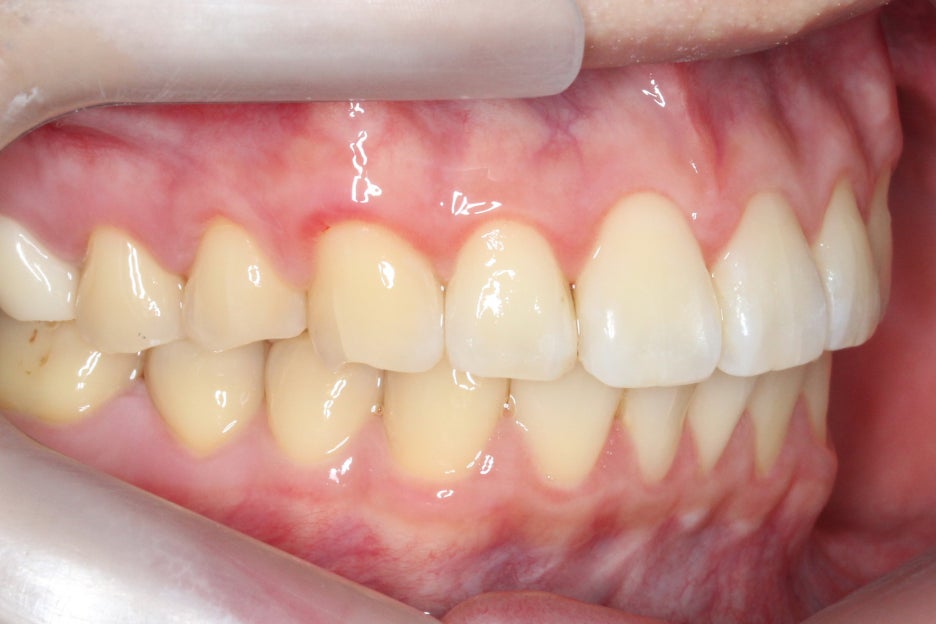

좌우의 교합평면을 보면 구치부의

교합은 비교적 양호한 편으로

부정교합 증상을 크게 나타나지 않는 모습이에요.

그러나 전치부의crowding과

중절치의 뻐드러짐이 심한 상태이기 때문에

삐뚤어진 11번 중절치를 바른 각도로

교정한 후 전치부의 crowding을

해결할 수 있도록 하였습니다.